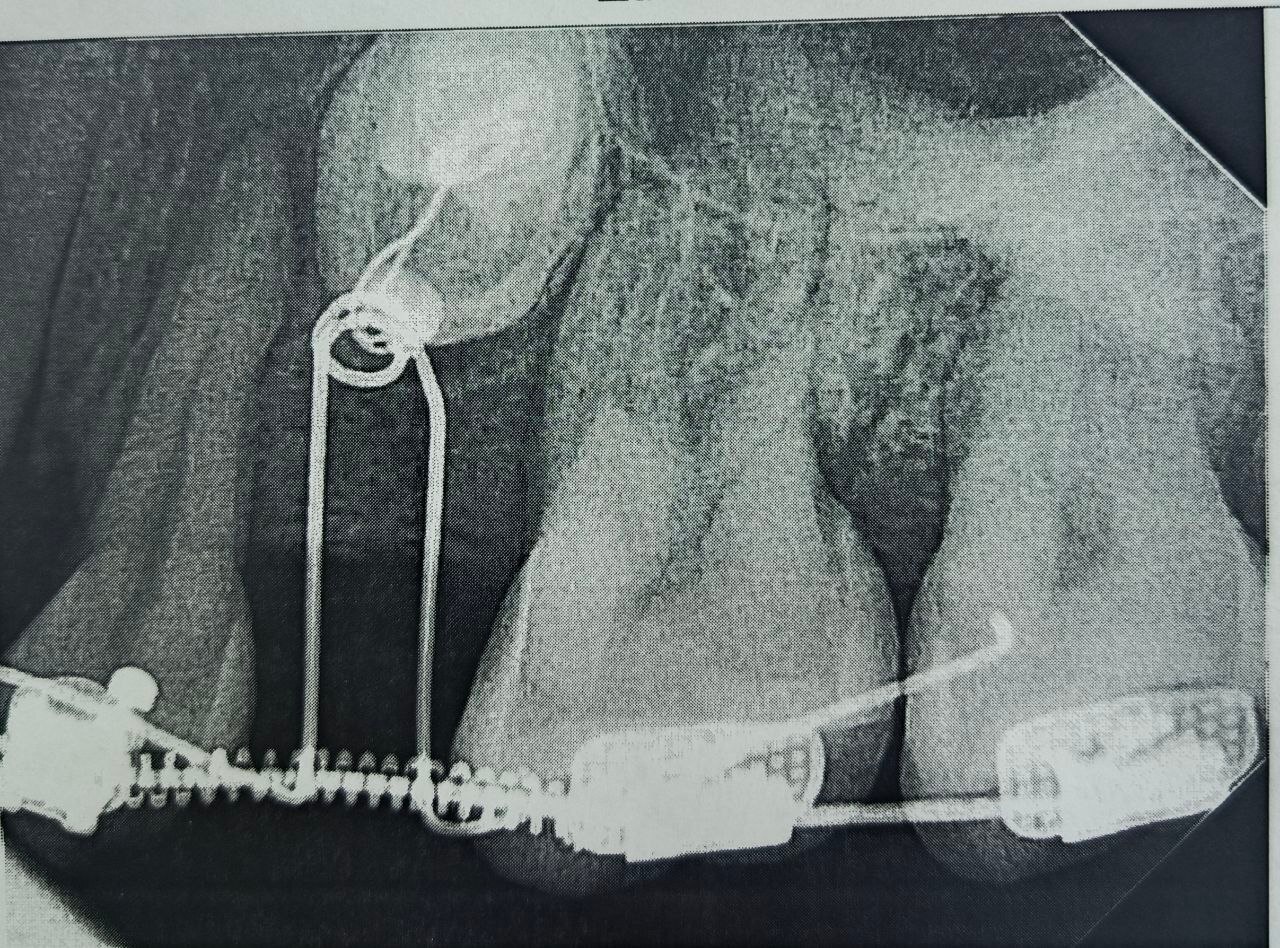

Сначала пациентке установили брекет-систему, полтора года с ее помощью в зубном ряду создавалось место. Когда пространство было подготовлено, хирурги провели операцию: раскрыли десну, чтобы обнажить коронки непрорезавшихся зубов, и зафиксировали на них специальные ортодонтические кнопки.

С помощью миниатюрных пружин и рычагов, подключенных к брекет-системе, зубы начали медленное движение.

На сегодняшний день один зуб уже полностью вышел из костной ткани и занял свое законное место. Второй успешно проходит последний барьер - кортикальную пластинку челюсти - и вскоре тоже встанет в ряд.